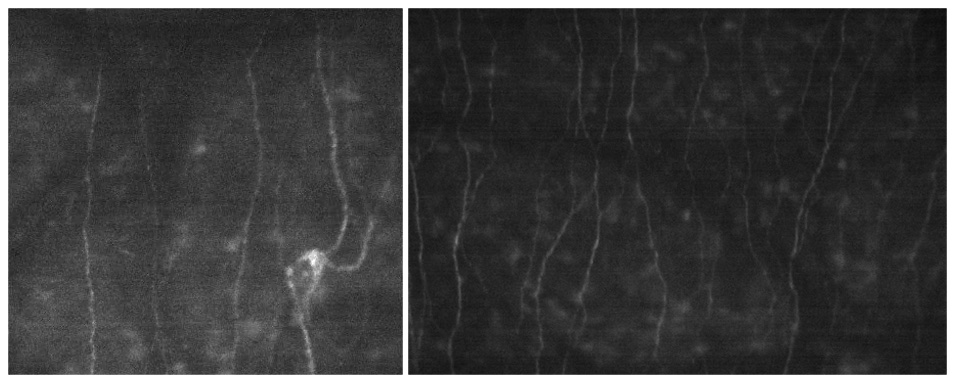

To further aid her efforts in identifying the true source of pain for her patients, Dr. Massaro-Giordano is using the CellChek C® wide-field scanning specular microscope to detect subtle differences in corneal nerve morphology. NYU Langone was the first institution in North America to acquire the state-of-the-art microscope, which is currently being used for research purposes only.

Currently, Dr. Massaro-Giordano is comparing images from patients with dry eye disease to those from healthy controls. “We’re looking for specific changes in the nerves: Are they diminished, trying to regenerate, or inflamed? Are there microneuromas?” she explains.

So far, her analysis suggests that patients with ocular misalignments have relatively normal-appearing nerves. By contrast, patients with pronounced nerve pain symptoms have nerves that appear more inflamed, diminished, or abnormal. “These can give us clues as to which direction we need to go,” she says.